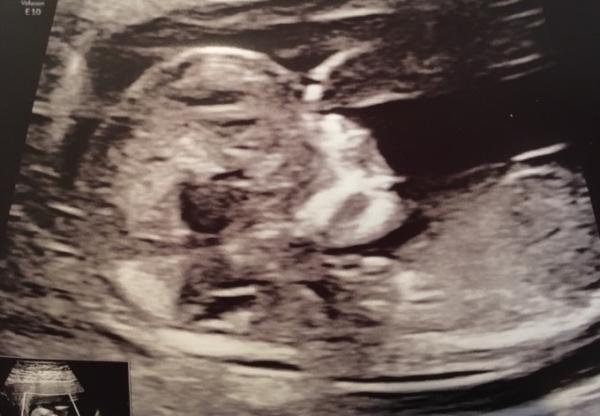

Huhu Waren Dienstag auch zum Ersttrimesterscreening. Laut Ultraschall alles unauffällig. Morgen kriege ich wohl den Anruf mit der Auswertung vom bluttest und kriege die Wahrscheinlichkeit mitgeteilt. Echt aufregend! Haben auch zwei Fotos mitbekommen...Auf dem einen fragt man sich: „Hat es keinen Mund?“ Auf dem anderen: „Was kommt den Krümel da aus dem Kopf? Ein Finger? Das sieht so groß aus...?“ Und was ist das für ein Knochen (?) da am Oberkiefer? Wenn die Zunge ein Knochen wäre, könnte man meinen, es streckt sie raus

Bild zu Neue Bilder von NFM - Forum für April - Mamis